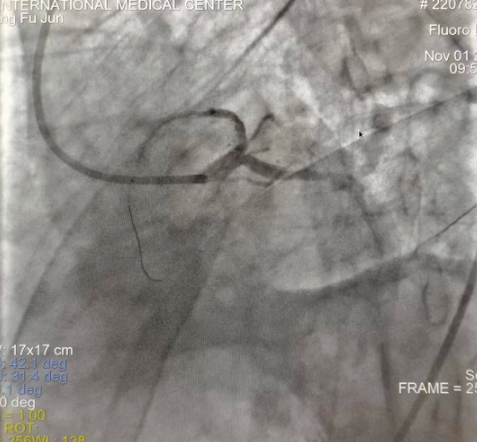

閉塞的血管再通時間取決于急救時長、轉運時長和治療時長,在前兩方面,醫(yī)院已為患者爭取了最短時間?;颊呒覍龠h在陜北,雖然已在趕來的路上,但最快抵達西安也要3小時,在與患者家屬電話溝通同意急診手術后,醫(yī)療總值班代家屬簽字,康曉軍在請示心臟病醫(yī)院王海昌院長及心臟內科CCU尚福軍主任后,積極進行術前準備。在沒有家屬陪同、沒有交費、沒有辦入院手續(xù)的情況下,患者經(jīng)胸痛中心綠色通道被送往心臟冠脈介入手術室,打通了完全閉塞的心臟前降支近段血管。